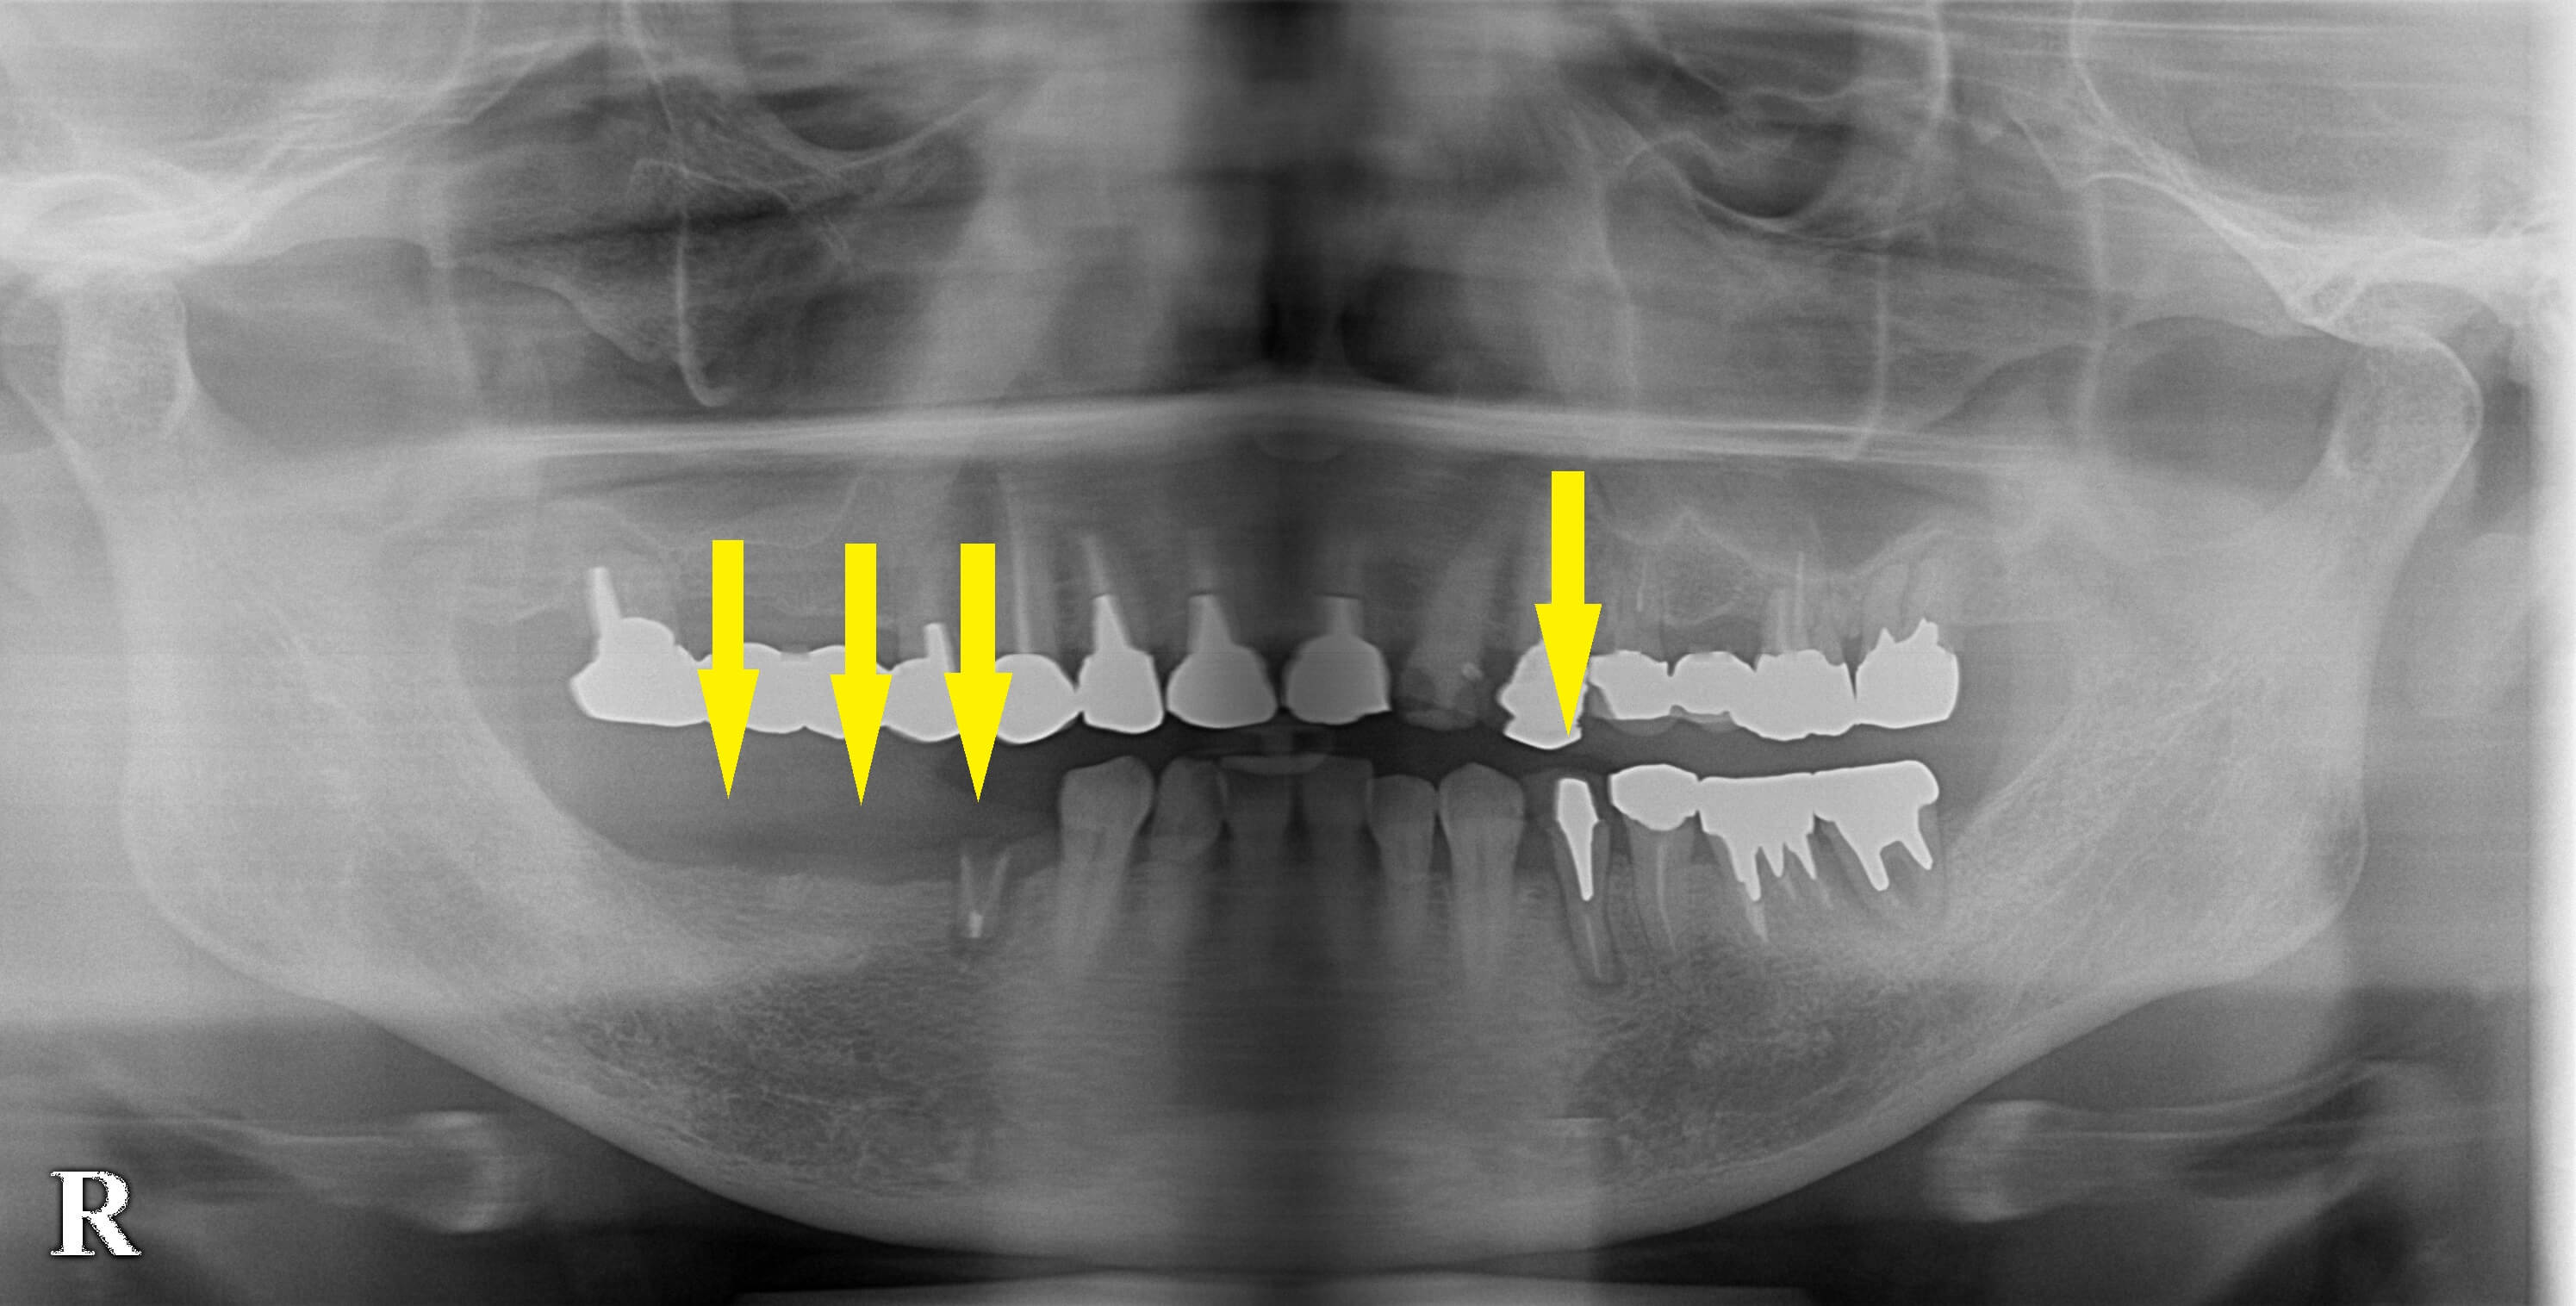

臼歯をインプラントで回復して咬みづらさを解消 今週のインプラント症例 2021.07.212026.01.19 患者様は名古屋在住の60代女性。 数年前から、右下顎の臼歯が抜けたままで過ごしておられたそうです。 最近になってさらにもう1本小臼歯の差し歯が取れていよいよ咬みづらくなったそうで、インプラント治療を決心されて来院されました。 差し歯が外れた右下顎の小臼歯と、歯根の周囲の骨が吸収されてしまった左下顎の小臼歯は抜歯させていただき、治癒を待ってのインプラント埋入としました。 本日、左下顎に1本、右下顎に3本のインプラント埋入を行いました。 症例・コラム一覧に戻る